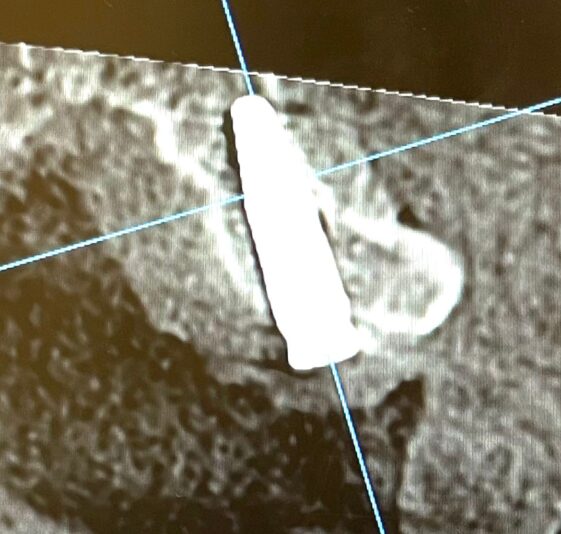

Good day everyone ! Recently I have placed an implant in the 23 region without using a guide. Patient has a prominent buccal exostosis and low smile line. However the bone apical to the bony exostosis is narrow. I made a mistake by focusing too much on getting the ideal screw channel axis and placed the implant too lingually.

While the cervical half of the fixture is well surrounded by thick labial bone but the apical half has nearly perforated the labial bone.

In this case, asethetic may not be a significant but in terms of the success rate of implant, but does thin or absent labial bone around the apical half could negatively impact the implant’s success rate?

This is a very common issue and it is great that you did not actually break through the labial plate. Although it looks very thin on the CBCT in that region, if you flapped it you might find that there is still bone covering the implant and that no exposure is present. (I am not advising you to flap it!)

I have actually seen a few studies about this, where the CBCT shows no to little bone but the implant is successful even after a decade. The main factor in these cases was the about of soft tissue. It being so apically I would not worry about it, learn from it and keep going. I see no reason why it would impact the success of the case. Like Ivan said, the buccal plate doesn’t seem to be perfed so you should be fine.